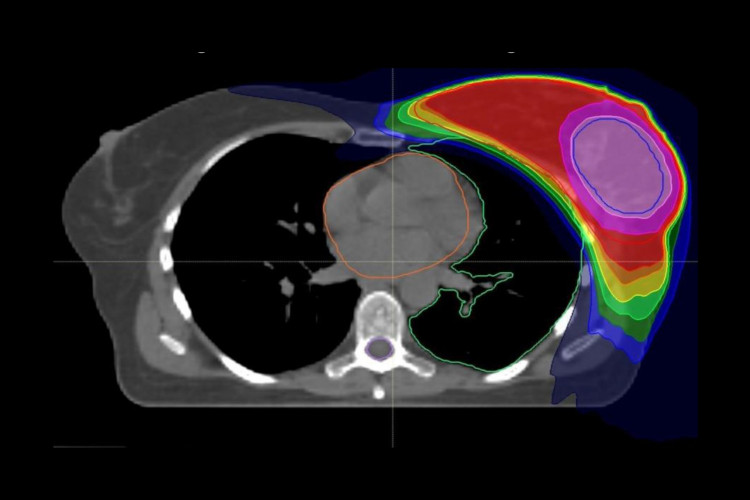

Nach der Brustkrebs-OP wird in der Regel zusätzlich zur Bestrahlung der gesamten Brust die unmittelbare Umgebung des entfernten Tumors gesondert intensiv bestrahlt. Diese „Boost"-Bestrahlung muss allerdings nicht zwangsläufig – wie bisher empfohlen – im Anschluss an die mehrwöchige Bestrahlung stattfinden. Sie ist ebenso wirksam, wenn sie simultan in ein modernes Bestrahlungskonzept integriert wird, wie eine im International Journal of Radiation Oncolocy • Biology • Physics veröffentlichte Studie unter Leitung der Radiologischen Universitätsklinik Heidelberg ergeben hat. Durch die integrierte Boost-Bestrahlung verkürzt sich die Strahlentherapie um rund 10 Tage auf fünf Wochen. Während der Nachbeobachtungszeit von fünf Jahren war das neue Bestrahlungskonzept in Behandlungs- und kosmetischem Ergebnis der Standartbehandlung gleichwertig. „Die kürzere Bestrahlungszeit ist für die Patientinnen eine deutliche Erleichterung und damit im Hinblick auf die Lebensqualität im Vorteil", sagt Erstautorin Privatdozentin Dr. Juliane Hörner-Rieber, Geschäftsführende Oberärztin der Abteilung Radioonkologie und Strahlentherapie an der Radiologischen Universitätsklinik Heidelberg.

Die aktuellen Leitlinien der Amerikanischen Gesellschaft für Radioonkologie (ASTRO) zur Strahlentherapie bei Brustkrebs empfehlen bislang noch die anschließende Boost-Bestrahlung. „Das liegt daran, dass es bisher noch keine belastbaren Daten zur Bewertung des integrierten Boosts gab", so Professor Dr. Dr. Jürgen Debus, Ärztlicher Direktor der Radiologischen Universitätsklinik und Letztautor der Studie. „Unsere Ergebnisse sind ein erster wichtiger Schritt zur evidenzbasierten Aktualisierung der Leitlinien." Insbesondere moderne Bestrahlungstechniken wie die sogenannte Intensitätsmodulierte Radiotherapie (IMRT), bei der Risikoorgane bestmöglich geschont werden können, haben der neuen Entwicklung den Weg geebnet. Inwieweit sich die Ergebnisse auf die seit rund drei Jahren zunehmend angewandte, verkürzte Radiotherapie der Brust übertragen lassen, ist Gegenstand aktueller Studien.